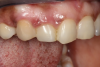

In the example case presented, the patient returned for evaluation 3 months after implant placement and delivery of the fiber-reinforced composite bridge, and the soft tissue at the site demonstrated adequate growth over the resin pontic (Figure 14). This would provide for a favorable esthetic outcome when the final implant-supported crown was ultimately delivered.

(14.) Three-month posttreatment close-up right lateral view of the final bridge. Note how the soft tissue at the site demonstrates adequate growth over the resin pontic, which will later translate into excellent esthetics for the implant-supported crown.

Figure 14